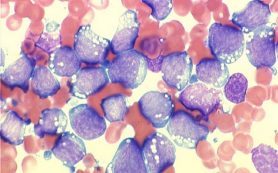

A study in mice combining two inhibitor drugs for treatment of chronic myeloid leukemia (CML) has revealed potential for not only stopping the disease completely, but also significantly lowering the cost for treatment. CML is a cancer of the white blood cells accounting for 20 percent of adult leukemia.

Researchers combined the BCR-ABL tyrosine kinase inhibitor (TKI), with another inhibitor drug known as venetoclax, and observed encouraging response and cure rates for both the chronic phase of the disease and its fatal end-stage phase called blast crisis. BCR-ABL inhibitors are the current standard-of-care treatment allowing most patients to remain in remission, but they do not entirely eradicate the cancer cells. In some patients, the cancer returns in a form that is untreatable. Approximately 100,000 patients in the U.S. are kept on life-long TKI therapy at a cost of $100,000 annually, a treatment that is unaffordable for many patients.